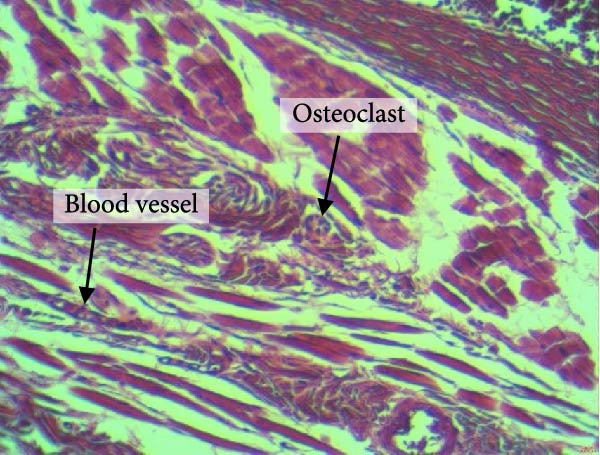

Figure 4 shows the periodontal tissue light‐microscopic findings in the study groups. As shown, the number of blood vessels, osteoclasts, and Howship’s lacunae was significantly higher in rats subjected to stress and CE injection for a 40‐day period, compared with others.

Figure 4H&E staining. Blood vessels and osteoclasts in different subgroups: (A) orthodontic treatment/CE injection/stress (chronic); (B) orthodontic treatment/CE injection/stress (acute); (C) no orthodontic treatment/CE injection/stress (chronic); (D) no orthodontic treatment/CE injection/stress (acute).(A)(B)(C)(D)